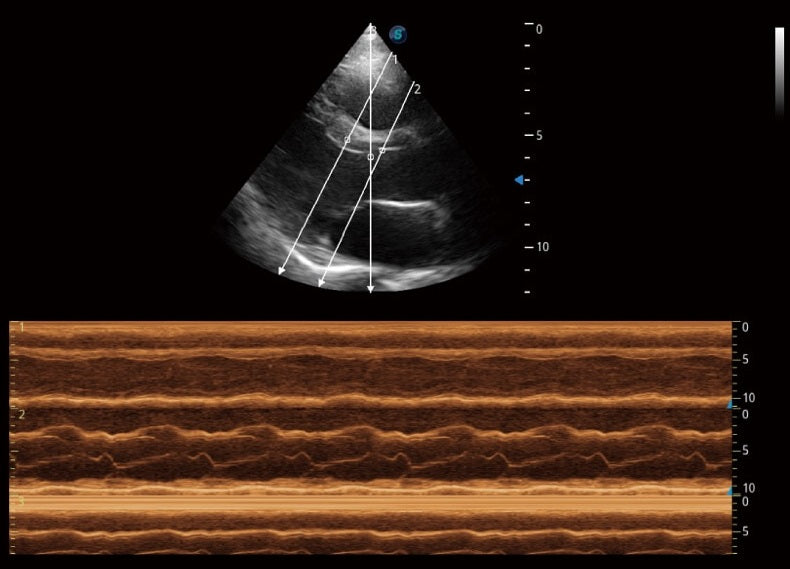

- Rendimiento superior: Imágenes excepcionales para abdomen, superficie y corazón.

- Herramientas cardíacas avanzadas: Evaluación completa de la función cardíaca.